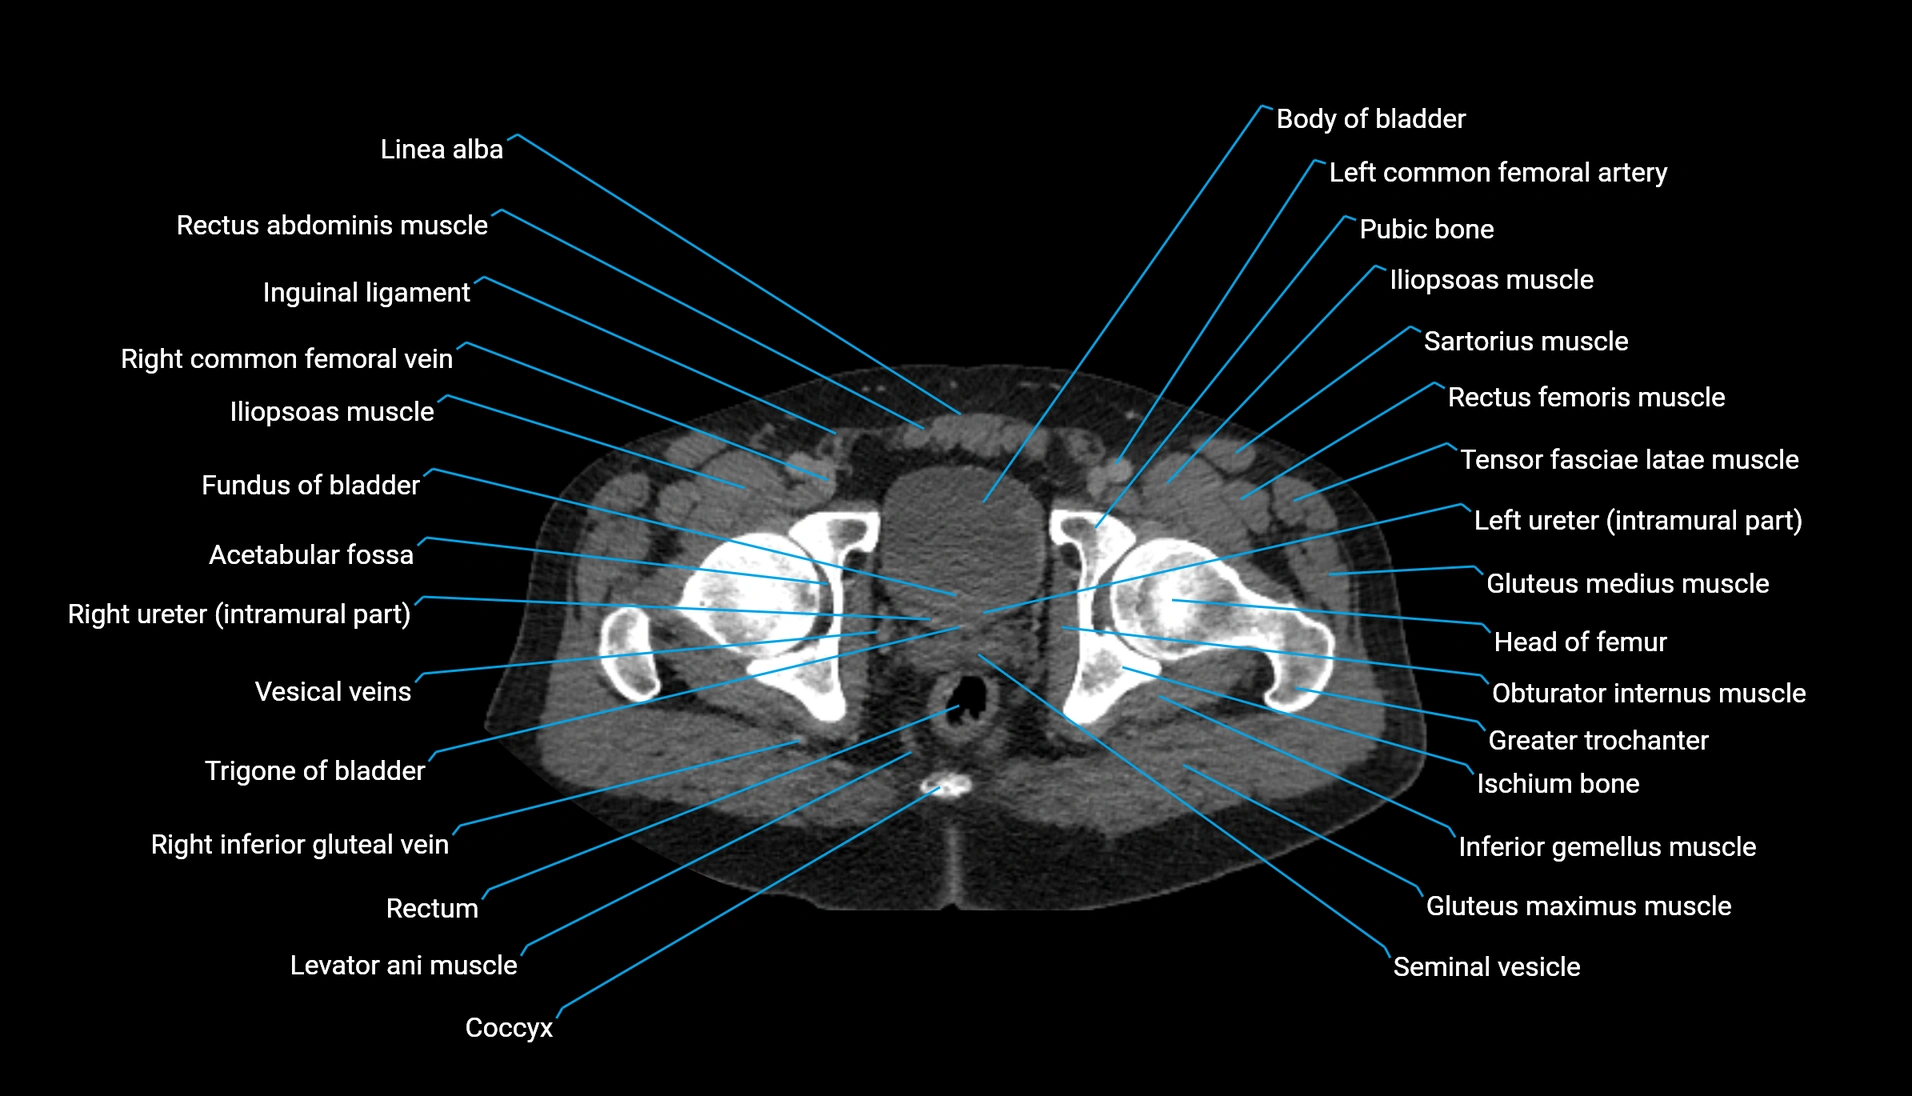

CT Appearance

Non-contrast CT:

-

Demonstrates cortical bone of acetabular rim in excellent detail

Detects fractures, dysplasia, retroversion, or bony overcoverage (pincer impingement)

3D reconstructions used in preoperative hip surgery planning

CT image